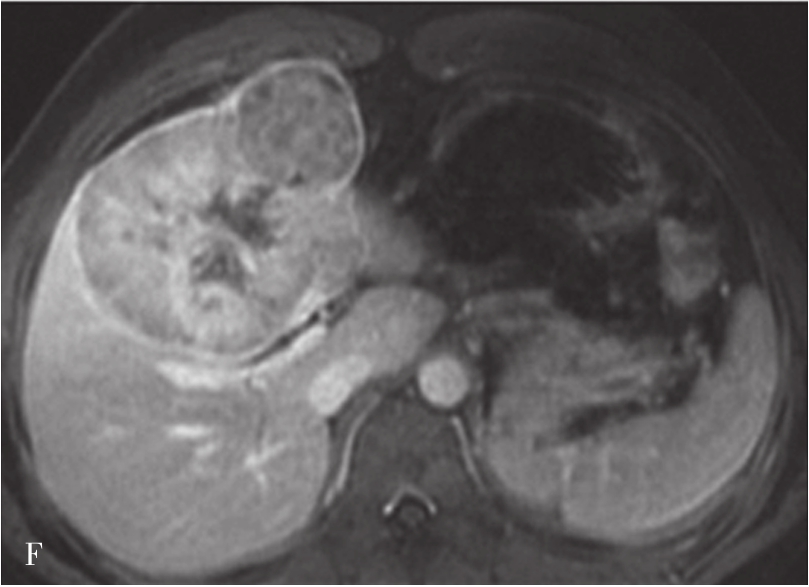

图5-21-42 HCC患者的MRI图像

A.T 2 WI脂肪抑制图像,可见肝右前叶内较大略高信号为主的病灶,内有点状更高信号影及中央低信号区,边界较清楚;B.600s/mm 2 时DWI图像,可见病灶为略高信号为主,中央略低信号;C.脂肪抑制图像,可见病灶为低信号影,边界较清楚,其内有一高信号影(箭头),为出血信号;D.增强扫描动脉期图像,可见病灶内轻微强化;E.可见门脉期图像病灶不均匀强化;F.可见延迟期图像病灶大部强化,中央无强化,假包膜清楚

HCC最常见的MRI表现为T 1 WI呈略低信号,T 2 WI呈略高信号,DWI呈高信号(图5-21-42)。有文献报道T 1 WI呈等信号者,多为分化较好的早期HCC,而脂肪变、出血、坏死、细胞内糖原沉积或铜沉积可导致病灶在T 1 WI上呈高信号,此外,在肝血色病基础上发生的HCC,由于肝实质在各脉冲序列图像上信号均很低,病灶一般都呈相对高信号。肿瘤假包膜可见于40%~70%的结节型和巨块型HCC。Gd-DTPA增强较为特征性的强化形式是对比剂“快进快出”,其原理为这些病灶70%的血供来自肝动脉,延迟相上出现宽0.5~3mm的包膜强化也颇具特征。采用特异性肝细胞摄取的对比剂,比如钆塞酸二钠(Gd-EOB-DTPA,普美显)不仅有其他钆类对比剂同样的动态增强外,在静脉注射10~30min内约有50%被正常肝细胞摄取,而不含正常肝细胞的HCC则很少或基本不摄取,而在肝特异性期呈低信号。有助于小HCC与肝硬化再生结节和其他良性病变的鉴别。大多数HCC在肝特异性期呈现相对低信号,但约10%的分化程度较好的HCC亦可呈等或高信号。